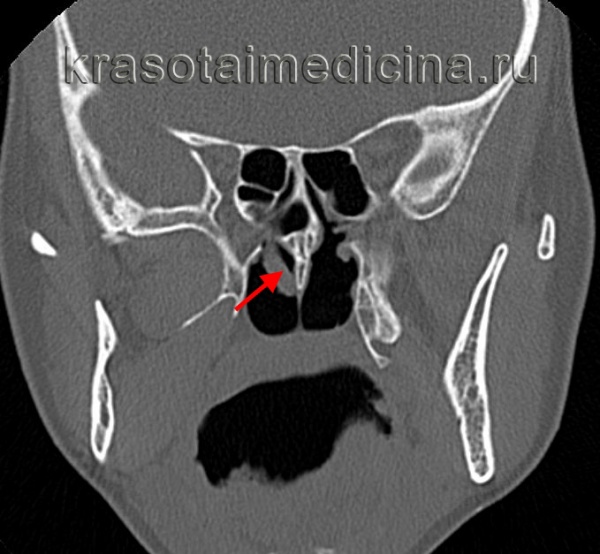

- Рентгеновское исследование ППН. Для оценки степени разрастания полипов носа проводится КТ околоносовых пазух. КТ-исследование в обязательном порядке проходят пациенты, которым предстоит хирургическое лечение полипов носа, поскольку результаты компьютерной томографии позволяют хирургу заранее определиться с объемом операции и разработать соответствующую тактику ее проведения. При отсутствии возможности для использования в диагностике компьютерной томографии состояние пазух исследуют при помощи рентгенографии.

- Томографические исследования. Для оценки характера разрастания полипов применяют КТ или МРТ околоносовых пазух. С их помощью также можно выявить анатомические дефекты (искривление перегородки, кисты в синусах, сужение и деформацию носовых ходов).

- КТ носовых пазух. Компьютерная томография выполняется для определения распространенности образований, оценки анатомического строения пазух и обнаружения дефектов. Исследование проводится перед хирургическим вмешательством для определения объема операции.